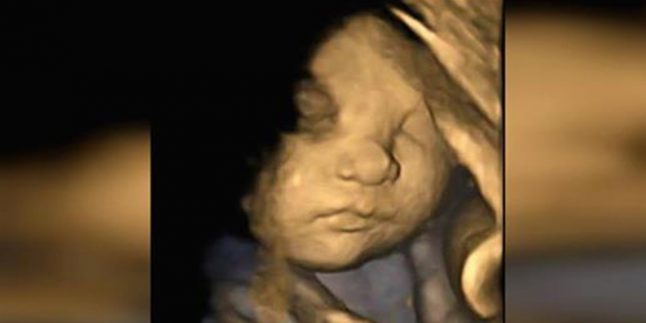

Avrupa İnsan Hakları Mahkemesi (AİHM), bebekleri ölmek üzere olan İngiliz ailenin, bebeğin yaşam desteğinin sonlandırmasına karşı çıkan talebini reddetti

Strazburg’ta bulunan Avrupa İnsan Hakları Mahkemesi, bebekleri ölmek üzere olan İngiliz aileden, bebeklerinin cuma günü Liverpool’da bulunan Alder Hey Çocuk Hastanesi’nde yaşam desteğinin sonlandırmasının ertelenmesi için bir başvuru aldığını duyurdu

Hastanede yatan 23 aylık Alfie Evans’ın ebeveynlerinin cuma günü gerçekleştirilmesi planlanan yaşam desteğinin sonlandırılmasının ertelenmesi ve çocuklarını tedavi için İtalya’ya götürülmesini “kabul edilemez” olarak nitelendirerek talebi reddetti.

Londra’daki İngiliz Yüksek Mahkemesi, geçen hafta gizemli bir dejeneratif nörolojik hastalıktan muzdarip olan Alfie Evans’ın tedavisine son verilebileceğine hükmetmişti.

Liverpool’daki Alder Hey Çocuk Hastanesi’ndeki uzmanlar, yaşam destek tedavisinin durması gerektiğini söyleyerek daha ileri tedavinin gereksiz olduğunu gösteren tıbbi kanıtların mahkeme tarafından kabul edildiğini belirtmişti.